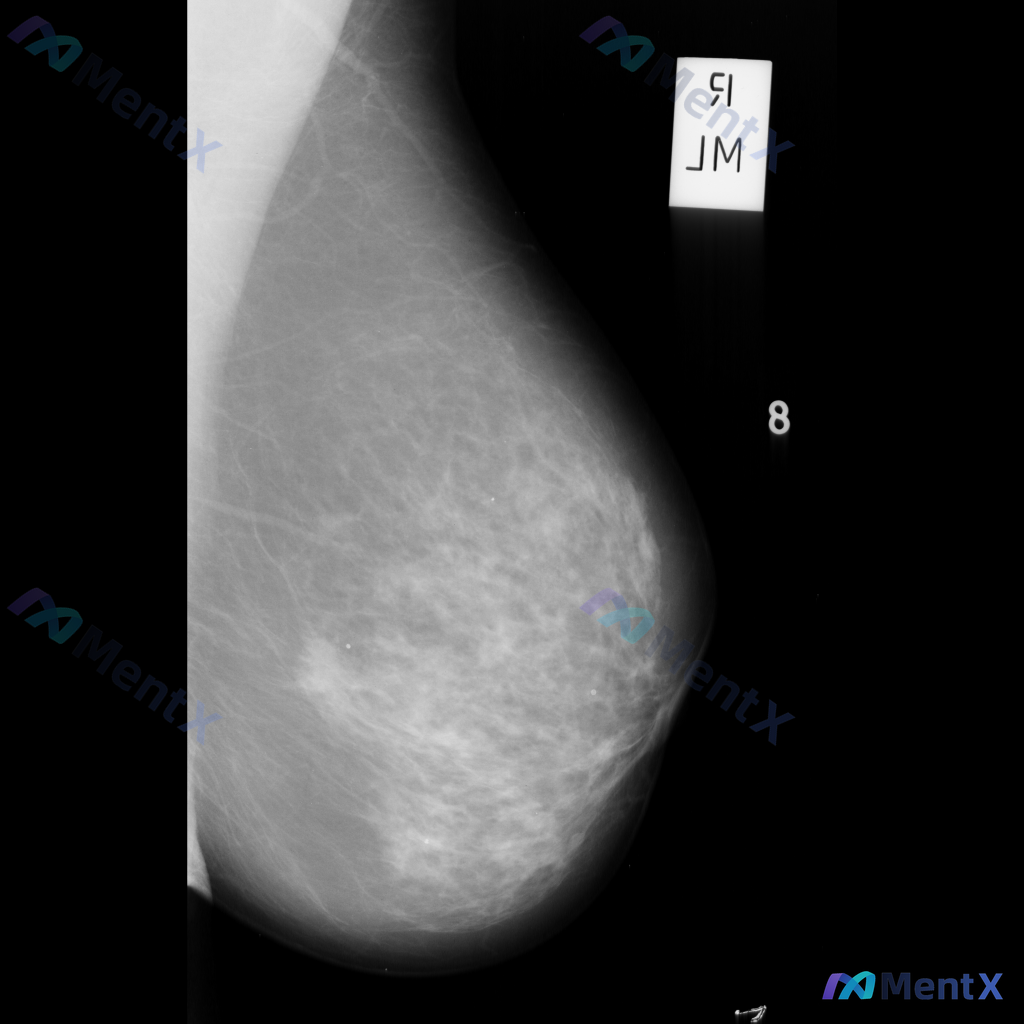

整理到一份右侧乳腺钼靶的影像资料,先和大家说一下表现: - 背景为不均匀致密型乳腺 - 右侧乳腺中部偏上区域可见局限性、成簇的细小多形性钙化 - 钙化区域周围可见局部密度略增高/结构异常的表现 目前还没有进一步的检查结果,单看这组影像表现,大家会优先往哪个方向考虑?后续评估思路是什么?

整理到一份单张乳腺钼靶影像的资料,分享给大家讨论: - 背景:乳腺整体为多量腺体型或致密型(BI-RADS C/D型可能) - 主要异常:在乳腺中下部略偏中央区域,可见局灶性不对称密度,或伴有轻度腺体结构紊乱 - 伴随征象:未见明确簇状/线样等可疑恶性钙化,无明确结构扭曲、皮肤增厚/回缩、乳头内陷等...

整理到一份乳腺钼靶的影像讨论资料,背景是不均匀致密型乳腺(BI-RADS C类),主要发现是一处不对称致密影——目前描述里没有提到明确的肿块、簇状微钙化或结构扭曲这类典型征象。 想跟大家讨论一下: 1. 单看这组表现,你第一反应会先往哪个方向考虑? 2. 这种情况下,你觉得最需要优先补充的评估是什么...